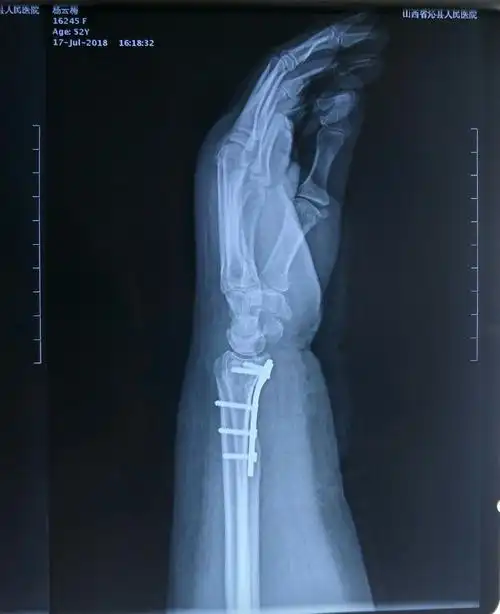

桡骨掌侧边缘剪切型骨折